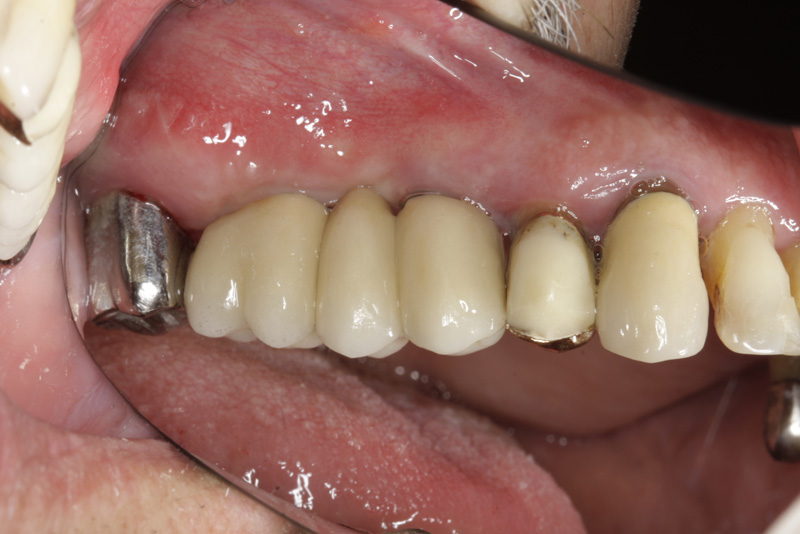

Náhrada jednoho zubu pomocí implantátu je možná také v postranním úseku chrupu. Při ztrátě většího počtu zubů ve frontálním nebo postranním úseku může být mezer uzavřena větším počtem jednotlivých implantátů.

Při ošetření pomocí jednotlivých implantátů zůstávají sousední zuby neporušené – intaktní. Při klasickém ošetření pomocí můstků musejí být tyto zuby obroušeny!

Protetické řešení může být pomocí můstku, který je kotvený na implantátech nebo pomocí jednotlivých korunek na implantátech.

V zásadě je možné do těchto můstků zařadit i přirozené zuby, zejména pokud je potřeba tyto zuby ošetřit proteticky

- korunkami. Korunky nebo můstky mohou být na implantáty nacementovány nebo přišroubovány.

Zdravé zuby zůstanou zachovány a přitom náhrady jsou pevné, jako na vlastních zubech